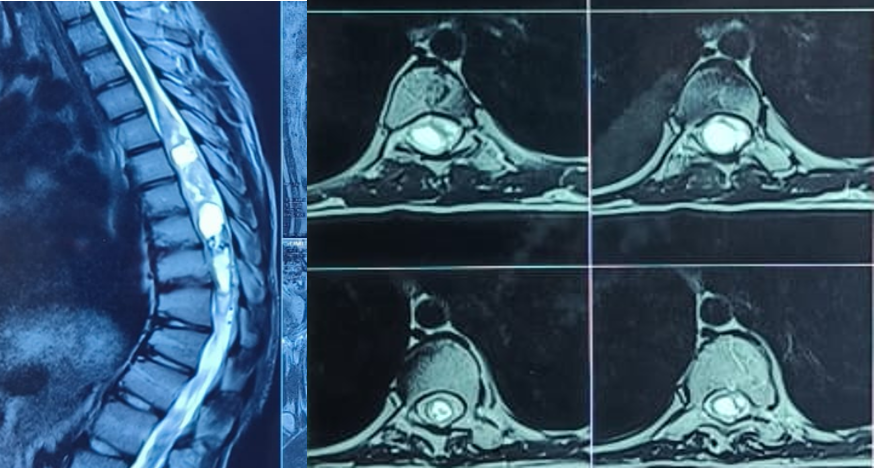

However, his lower limb deep tendon reflexes were exaggerated with grade 3+. Magnetic resonance imaging (MRI) revealed well defined expansile, intramedullary predominantly cystic lesion extending from D5 to D10 spinal cord levels with moderately enhancing solid component, along with structural abnormalities (Fig. 3). These features were suggestive of an intramedullary neoplastic lesion likely to be astrocytoma. Surgical plan was as follows; tumor resection with deformity correction and further management based on the biopsy report.

Figure 3: Magnetic resonance imaging demonstrating well-defined, mildly expansile, intramedullary cystic lesion extending from D5 to D10 levels with moderately enhancing solid components.